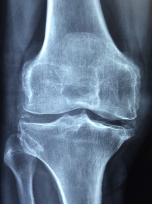

무릎 관절에 좋은 음식 무릎 관절 관리 방법 등 정보에 대해 알아보도록 하겠습니다. 무릎 관절은 우리 몸에서 가장 중요한 부위 중 하나입니다. 다리를 지탱하고, 움직임을 제공하는 기능을 수행합니다. 무릎 관절은 대개 체중과 운동에 의해 과부하가 걸리기 때문에, 연령과 상관없이 다양한 질환과 손상이 발생하기 쉽습니다. 무릎 관절 질환에는 퇴행성 관절염, 무릎 관절염, 슬관절 연골손상 등이 있습니다. 이러한 질환은 무릎 관절 통증, 붓기, 운동 제한 등의 증상을 유발합니다. 무릎 관절 건강을 유지하기 위해서는 적절한 운동, 올바른 식습관, 적절한 체중 유지, 적절한 자세 등이 필요합니다. 무릎 관절 질환의 예방과 관리를 위해서는 정기적인 건강 검진과 치료가 필요합니다.

무릎 관절염의 원인은 여러 가지가 있지만, 가장 일반적인 원인은 연령, 체중, 유전적인 요인, 부상, 직업적 요인, 불규칙한 운동 등이 있습니다.

- 연령: 노화로 인해 무릎 관절 손상이 발생할 가능성이 높습니다. 연령이 들면서 연골이 더 얇아지고 윤활유 분비가 감소하게 되어 무릎 관절의 충격 흡수 기능이 감소합니다.

- 체중: 과체중은 무릎 관절에 대한 부담을 높이며, 무릎 관절의 염증을 일으키고 무릎 관절염 발병 위험을 높입니다.

- 유전적 요인: 유전적 요인도 무릎 관절염의 원인 중 하나입니다. 가족력이 있는 경우 무릎 관절염 발병 위험이 높아집니다.

- 부상: 무릎 관절 부상은 무릎 관절염의 발병 위험을 높입니다. 특히, 골절, 연골손상, 인대 손상 등이 무릎 관절염을 일으키는 원인이 될 수 있습니다.

- 직업적 요인: 직업적 요인으로 인해 무릎 관절 부담이 커지면 무릎 관절염 발병 위험이 높아집니다. 예를 들어, 무릎을 자주 굽히거나 일어설 필요가 있는 직업, 장시간 서 있는 직업 등이 그러합니다.

- 불규칙한 운동: 무릎 관절 부하를 지나치게 높이는 불규칙한 운동은 무릎 관절의 염증을 유발합니다.

무릎 관절염은 위와 같은 여러 요인들이 복합적으로 작용하여 발생할 수 있습니다. 따라서 무릎 관절염 예방 및 치료를 위해서는 건강한 식습관과 운동 습관을 유지하며, 무릎 관절에 대한 적절한 관리가 필요합니다.